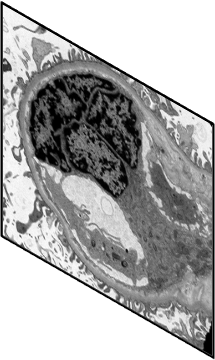

With the rapid development of self-supervised learning (e.g., contrastive learning), the importance of having large-scale images (even without annotations) for training a more generalizable AI model has been widely recognized in medical image analysis. However, collecting large-scale task-specific unannotated data at scale can be challenging for individual labs. Existing online resources, such as digital books, publications, and search engines, provide a new resource for obtaining large-scale images. However, published images in healthcare (e.g., radiology and pathology) consist of a considerable amount of compound figures with subplots. In order to extract and separate compound figures into usable individual images for downstream learning, we propose a simple compound figure separation (SimCFS) framework without using the traditionally required detection bounding box annotations, with a new loss function and a hard case simulation. Our technical contribution is four-fold: (1) we introduce a simulation-based training framework that minimizes the need for resource extensive bounding box annotations; (2) we propose a new side loss that is optimized for compound figure separation; (3) we propose an intra-class image augmentation method to simulate hard cases; and (4) to the best of our knowledge, this is the first study that evaluates the efficacy of leveraging self-supervised learning with compound image separation. From the results, the proposed SimCFS achieved state-of-the-art performance on the ImageCLEF 2016 Compound Figure Separation Database. The pretrained self-supervised learning model using large-scale mined figures improved the accuracy of downstream image classification tasks with a contrastive learning algorithm. The source code of SimCFS is made publicly available at https://github.com/hrlblab/ImageSeperation.